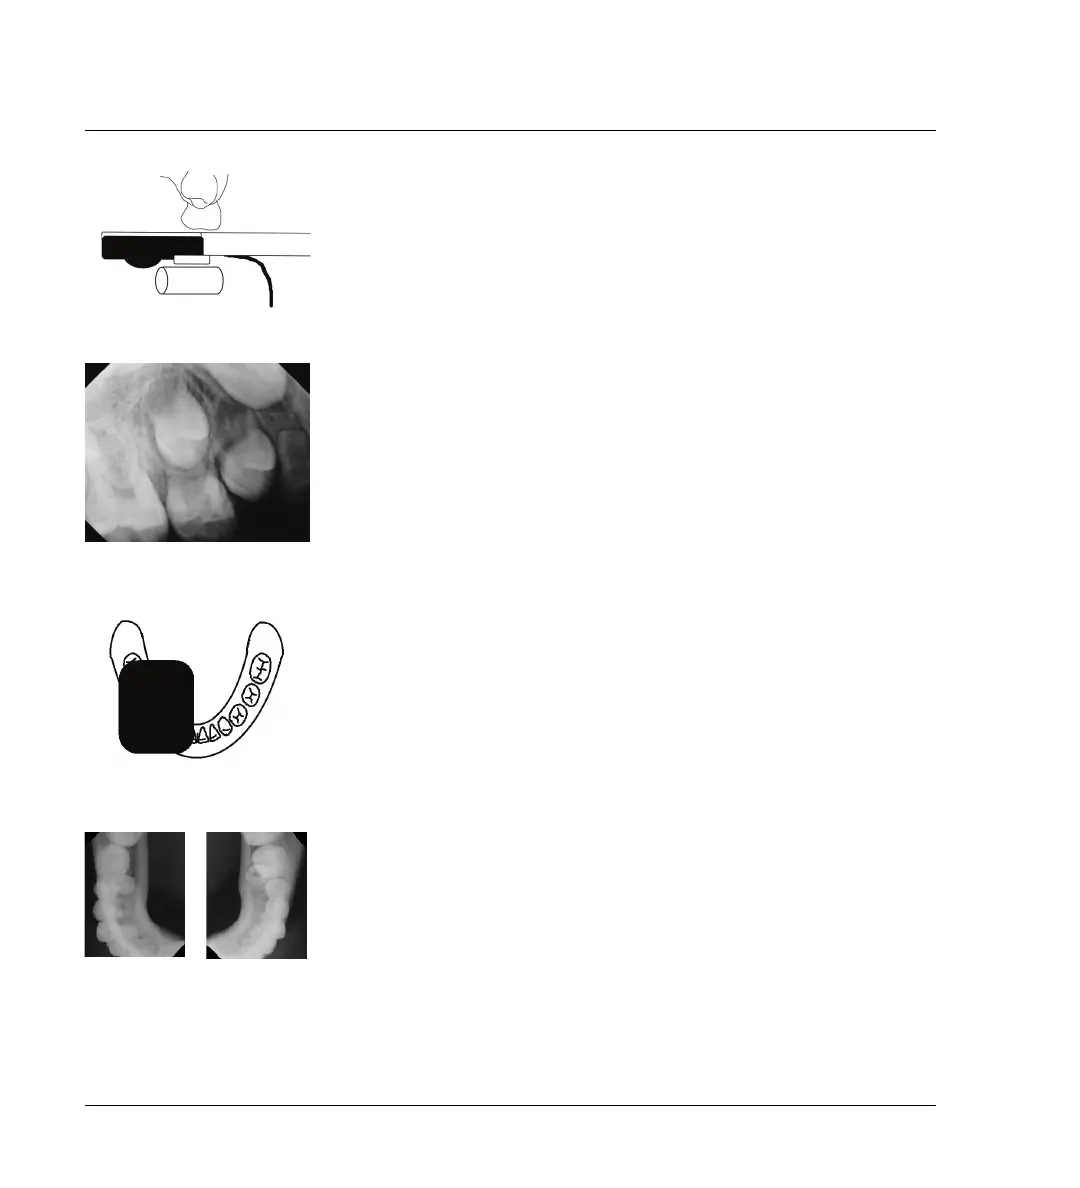

Technique d'occlusion modifiée

Placez le capteur parallèlement au plan occlusal et ajoutez un rouleau de

coton pour assurer la protection, le confort et le soutien. Demandez à

l'enfant de fermer la bouche doucement. Utilisez la technique de

bissection d'angle standard pour saisir l'image.

Images à deux expositions

Dans certains cas, vous pourriez avoir besoin de placer le capteur dans le

sens de la largeur, de l'avant à l'arrière, sur chaque moitié de l'arche et

d'ensuite répéter pour l'autre moitié.

Dans l'un et l'autre cas, le capteur est placé parallèlement au plan occlusal

et un rouleau de coton est ajouté pour assurer la protection, le confort et le

soutien. Demandez à l'enfant de fermer la bouche doucement. Utilisez la

technique d'occlusion standard pour saisir l'image.